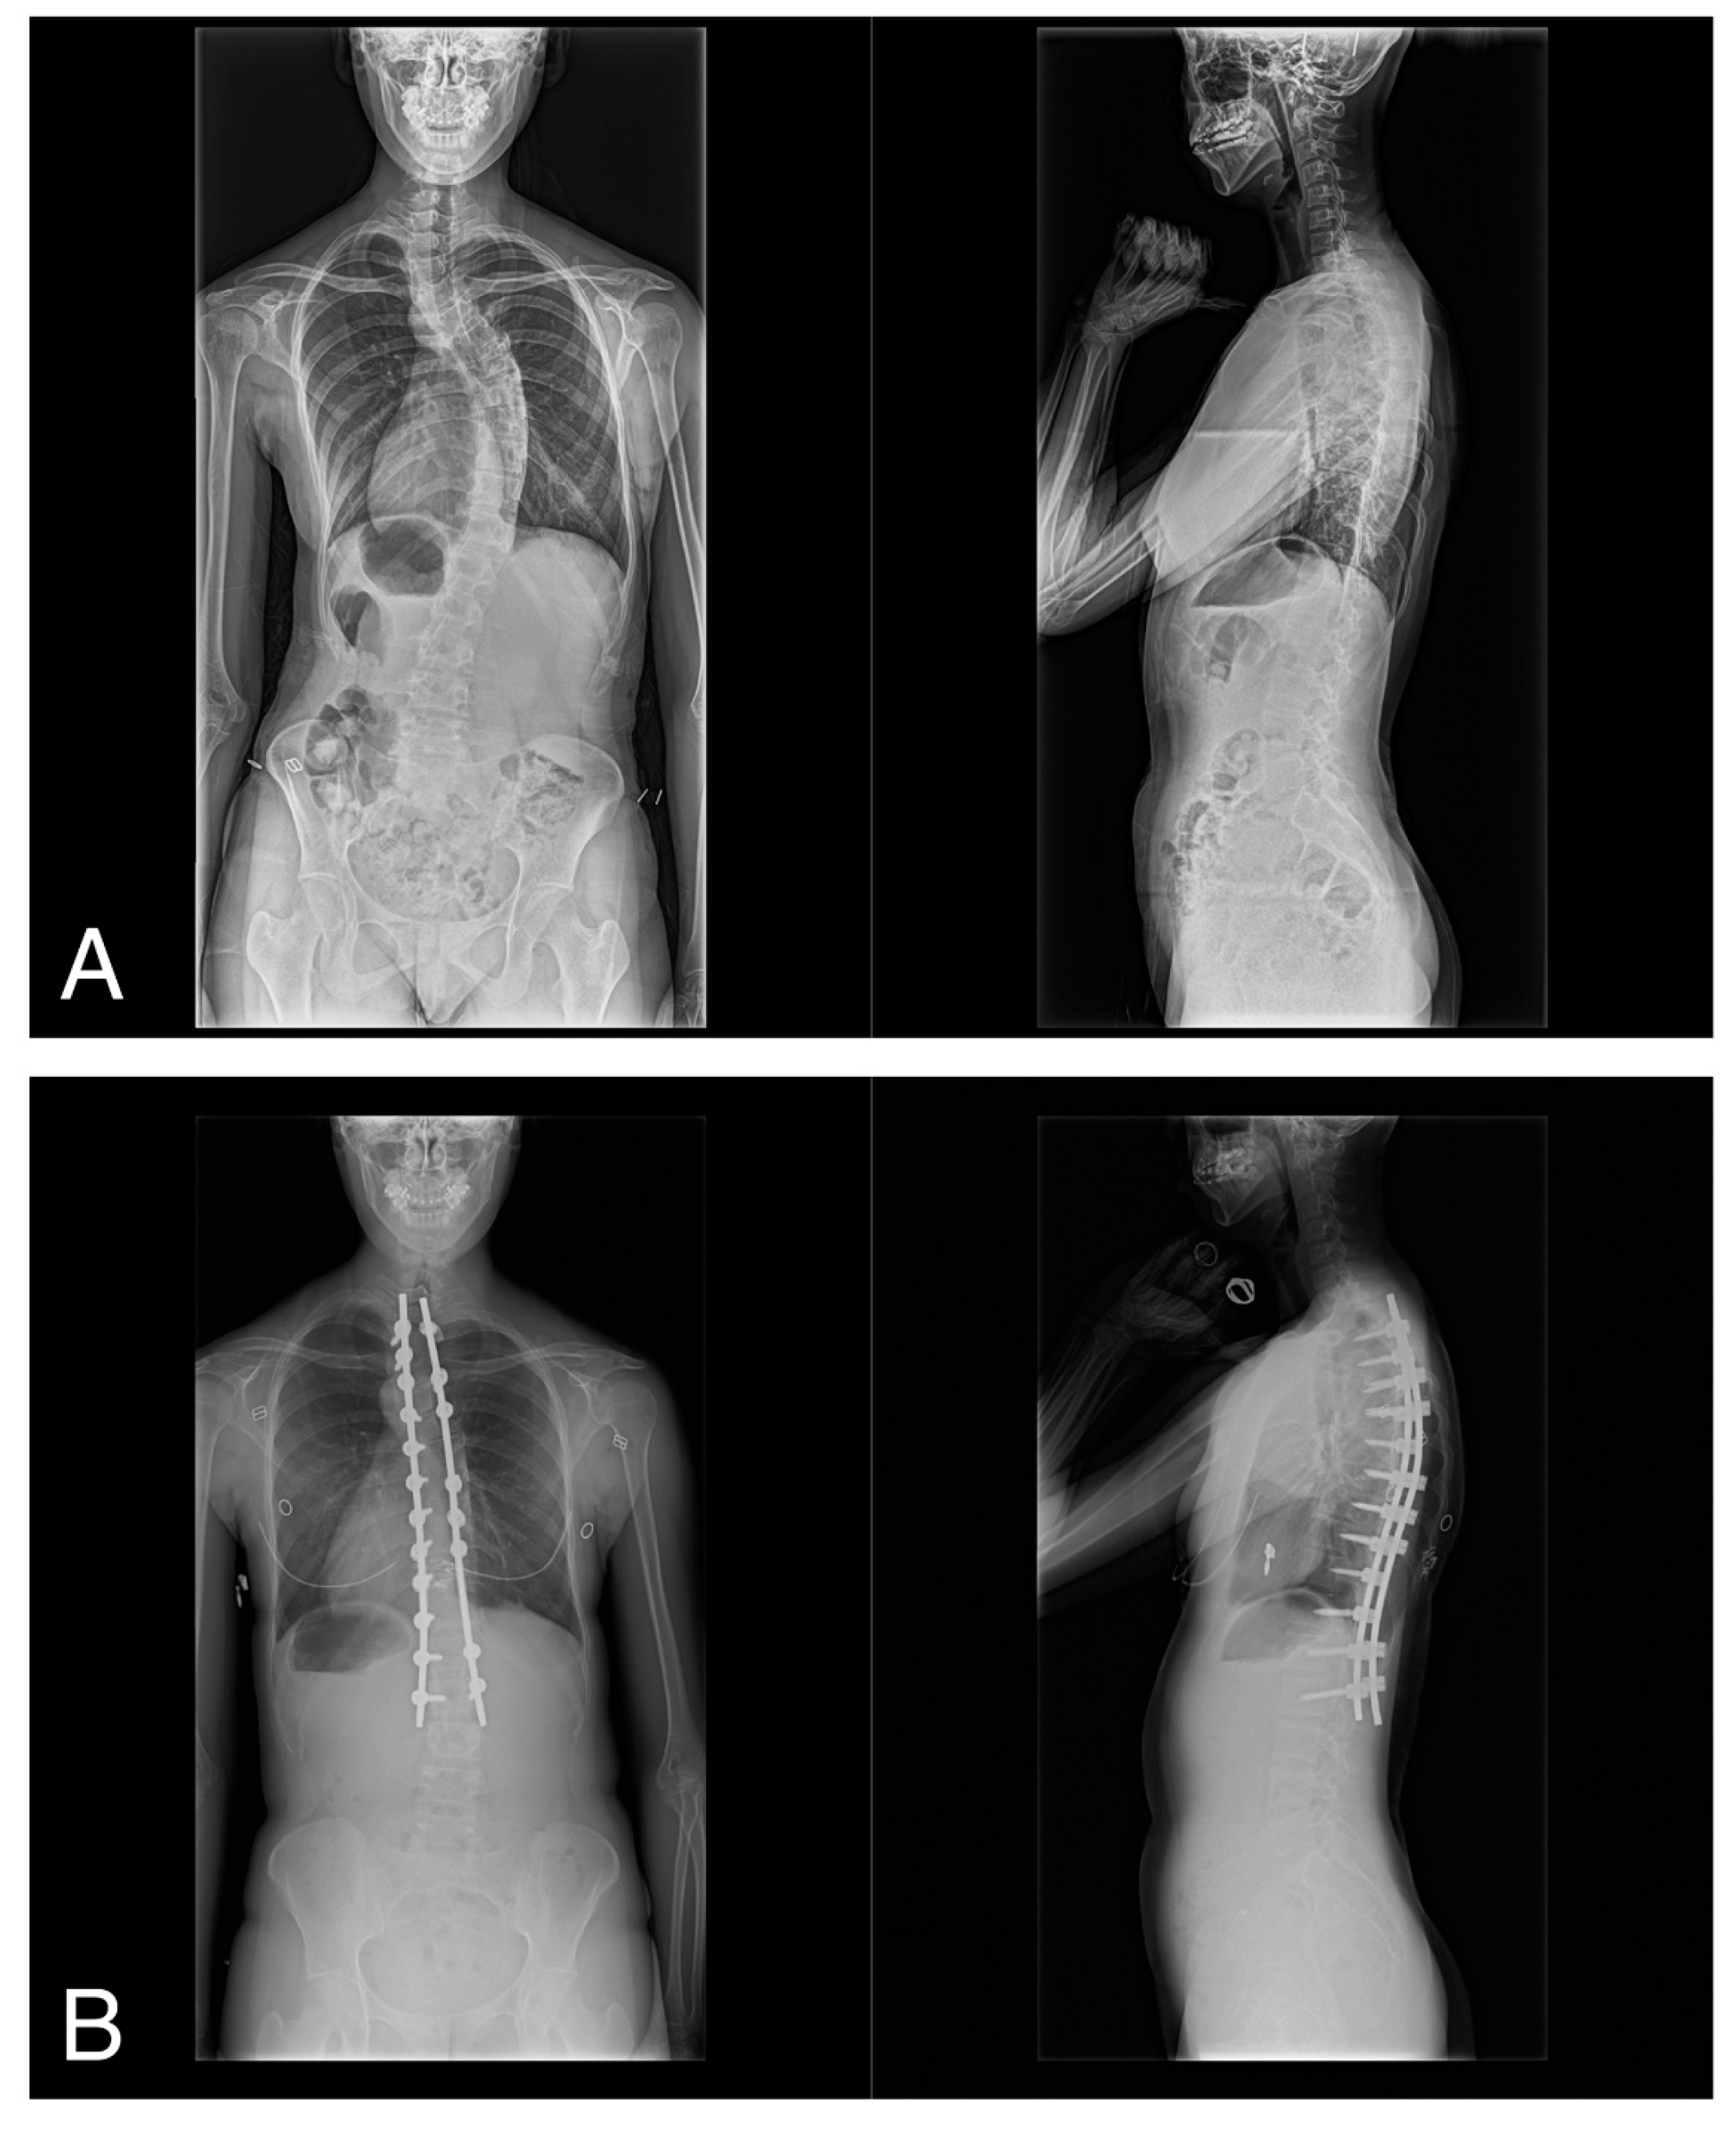

2.4. Radiographic Evaluation